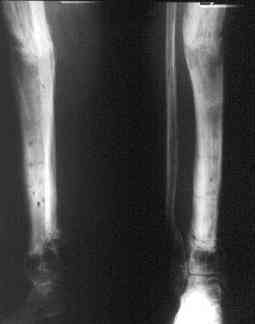

Огнестрельный дефект костей и передней группы мышц, поступил с юнилатеральным аппаратом, стабильность плохая, из раны обильное гнойное

отделяемое. #1;#2. Стержневой апп. снят, наложен апп. Илизарова, дренажно-ирригационная система промывки раны. #3; #4. После стихания инфекции,